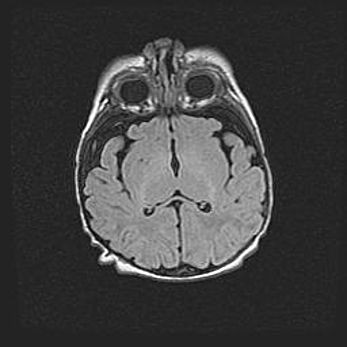

Открытая гидроцефалия.

Возраст: 9 месяцев 12 дней

Вес: 6800 г

Пол: мужской

Окружность головы: 41,5 см

Срок гестации: 28 недель

Гидроцефалия головного мозга у новорожденных имеет характерный признак: опережающий рост окружности головы приводит к визуально хорошо определяемой гидроцефальной форме сильно увеличенного в объёме черепа. Детские неврологи определяют следующие симптомы гидроцефалии у грудничков: выбухающий напряжённый родничок, частое запрокидывание головы, смещение глазных яблок к низу.